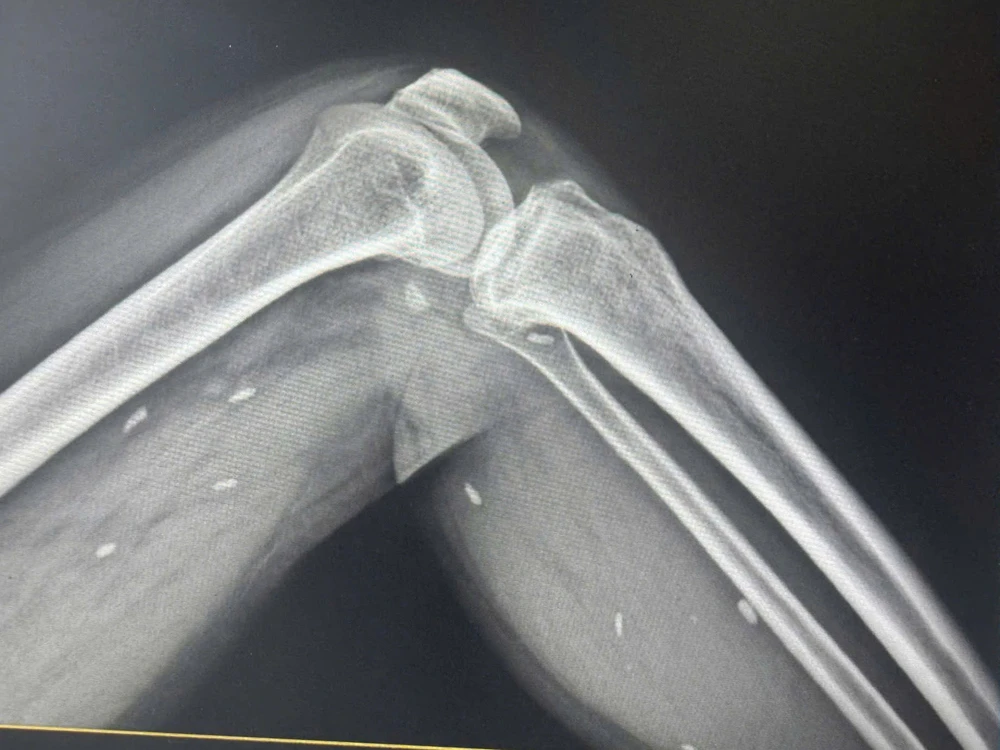

Nhiều kén sán nằm trong mô vùng xương đùi và cẳng chân.

Qua kết quả chụp X- quang, BS Đỗ Hồng Thanh, Phó Giám đốc Trung tâm Y tế khu vực Thạch Hãn, cho biết phát hiện nhiều kén sán kích thước như hạt gạo nằm rải rác ở các mô vùng xương đùi và cẳng chân bệnh nhân.